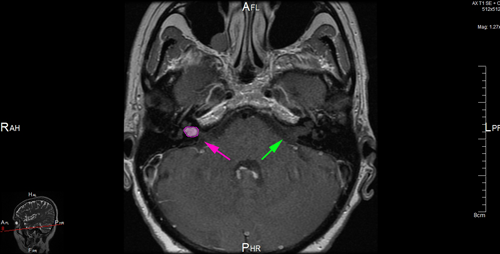

Αιθουσαίο σβάννωμα αριστερά (κόκκινο περίγραμμα). Φυσιολογικός έσω ακουστικός πόρος δεξιά (πράσινο βέλος), ακουστικό όργανο (κοχλίας) και όργανο ισορροπίας (λαβύρινθος) με κυανό βέλος. |